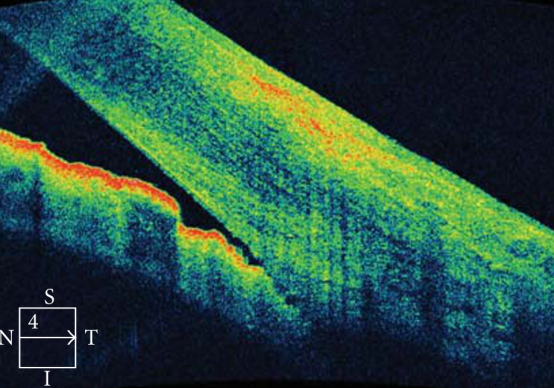

Рисунок «Карта толщины сетчатки в макулярной области при диабетическом макулярном отеке»